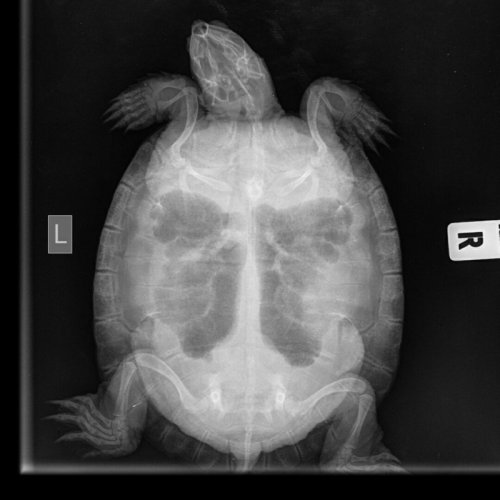

Podolnyi Ваше имя: Подольный Константин Локация: Украина, Днепр Опубликовано: 27 июня 2020 Опубликовано: 27 июня 2020 @_Pineapple_ рентген есть возможность сделать ? Вентродорсальная и правая латеральная

_Pineapple_ Ваше имя: Лежнина Анастасия Локация: Россия Томск Опубликовано: 1 июля 2020 Автор Опубликовано: 1 июля 2020 @Podolnyi Здравствуйте. Черепаха теперь спокойно погружается и даже съела кусок мяса, который я ей предложила (небольшой, я просто проверяла, станет ли есть). Сделали рентген.

Podolnyi Ваше имя: Подольный Константин Локация: Украина, Днепр Опубликовано: 2 июля 2020 Опубликовано: 2 июля 2020 У черепахи выраженный метеоризм (вздутие) жкт. Кальций начать снова будет, через неделю от сегодняшнего дня, по той же схеме. заставлять ее двигаться и делайте вибротерапию по 30 минут 2 раза в день. Яиц и фолликулов я не наблюдаю, но это не означает, что нет последних.